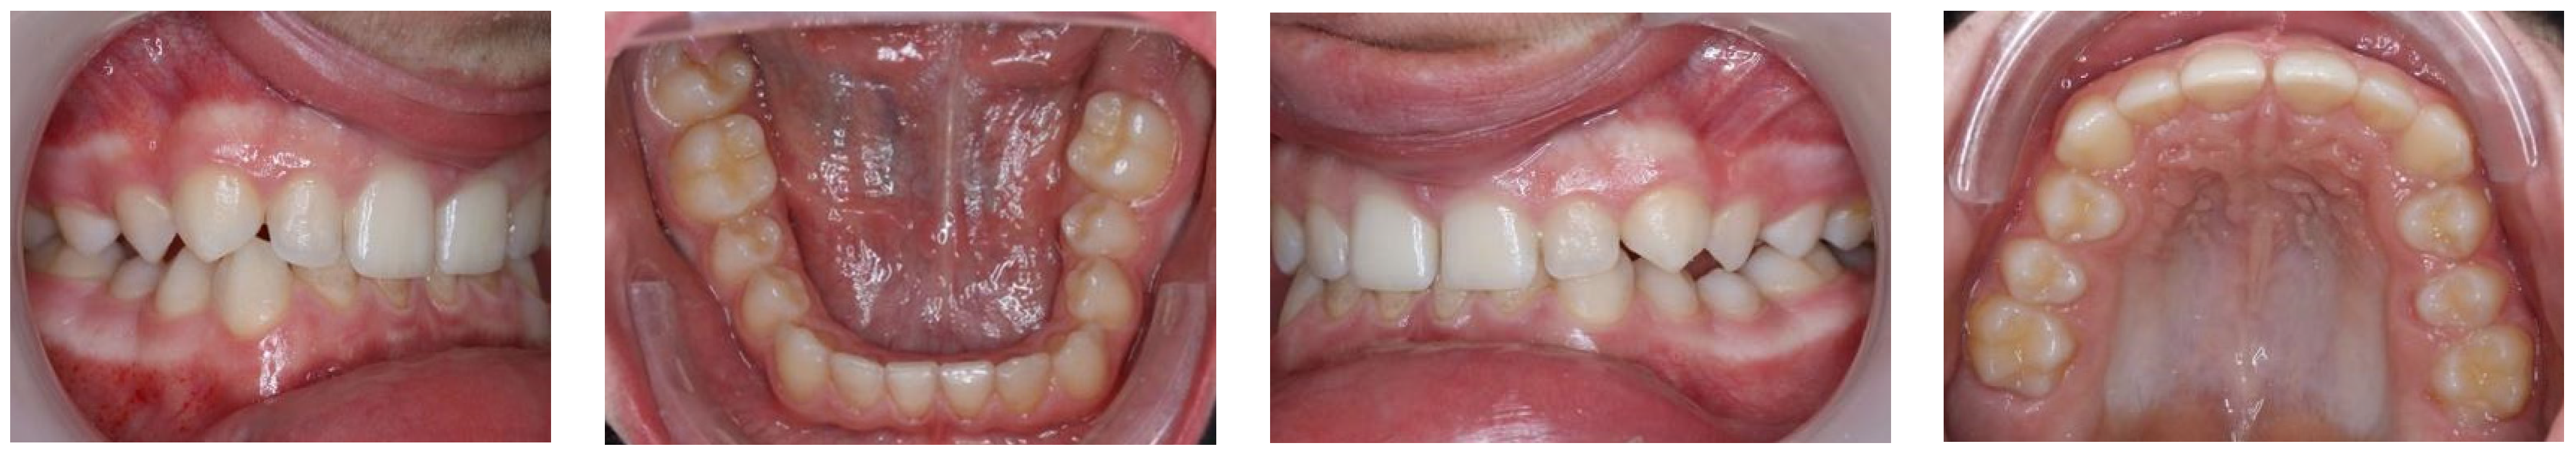

| Characteristics | Previous Studies | This Study |

|---|---|---|

| sex | 3 boys, 1 girl | a boy |

| mental retardation | 4/4 | + |

| speech disorders | 3/4 | + |

| facial dysmorphism | 4/4 | + |

| malocclusion | 4/4 | + |